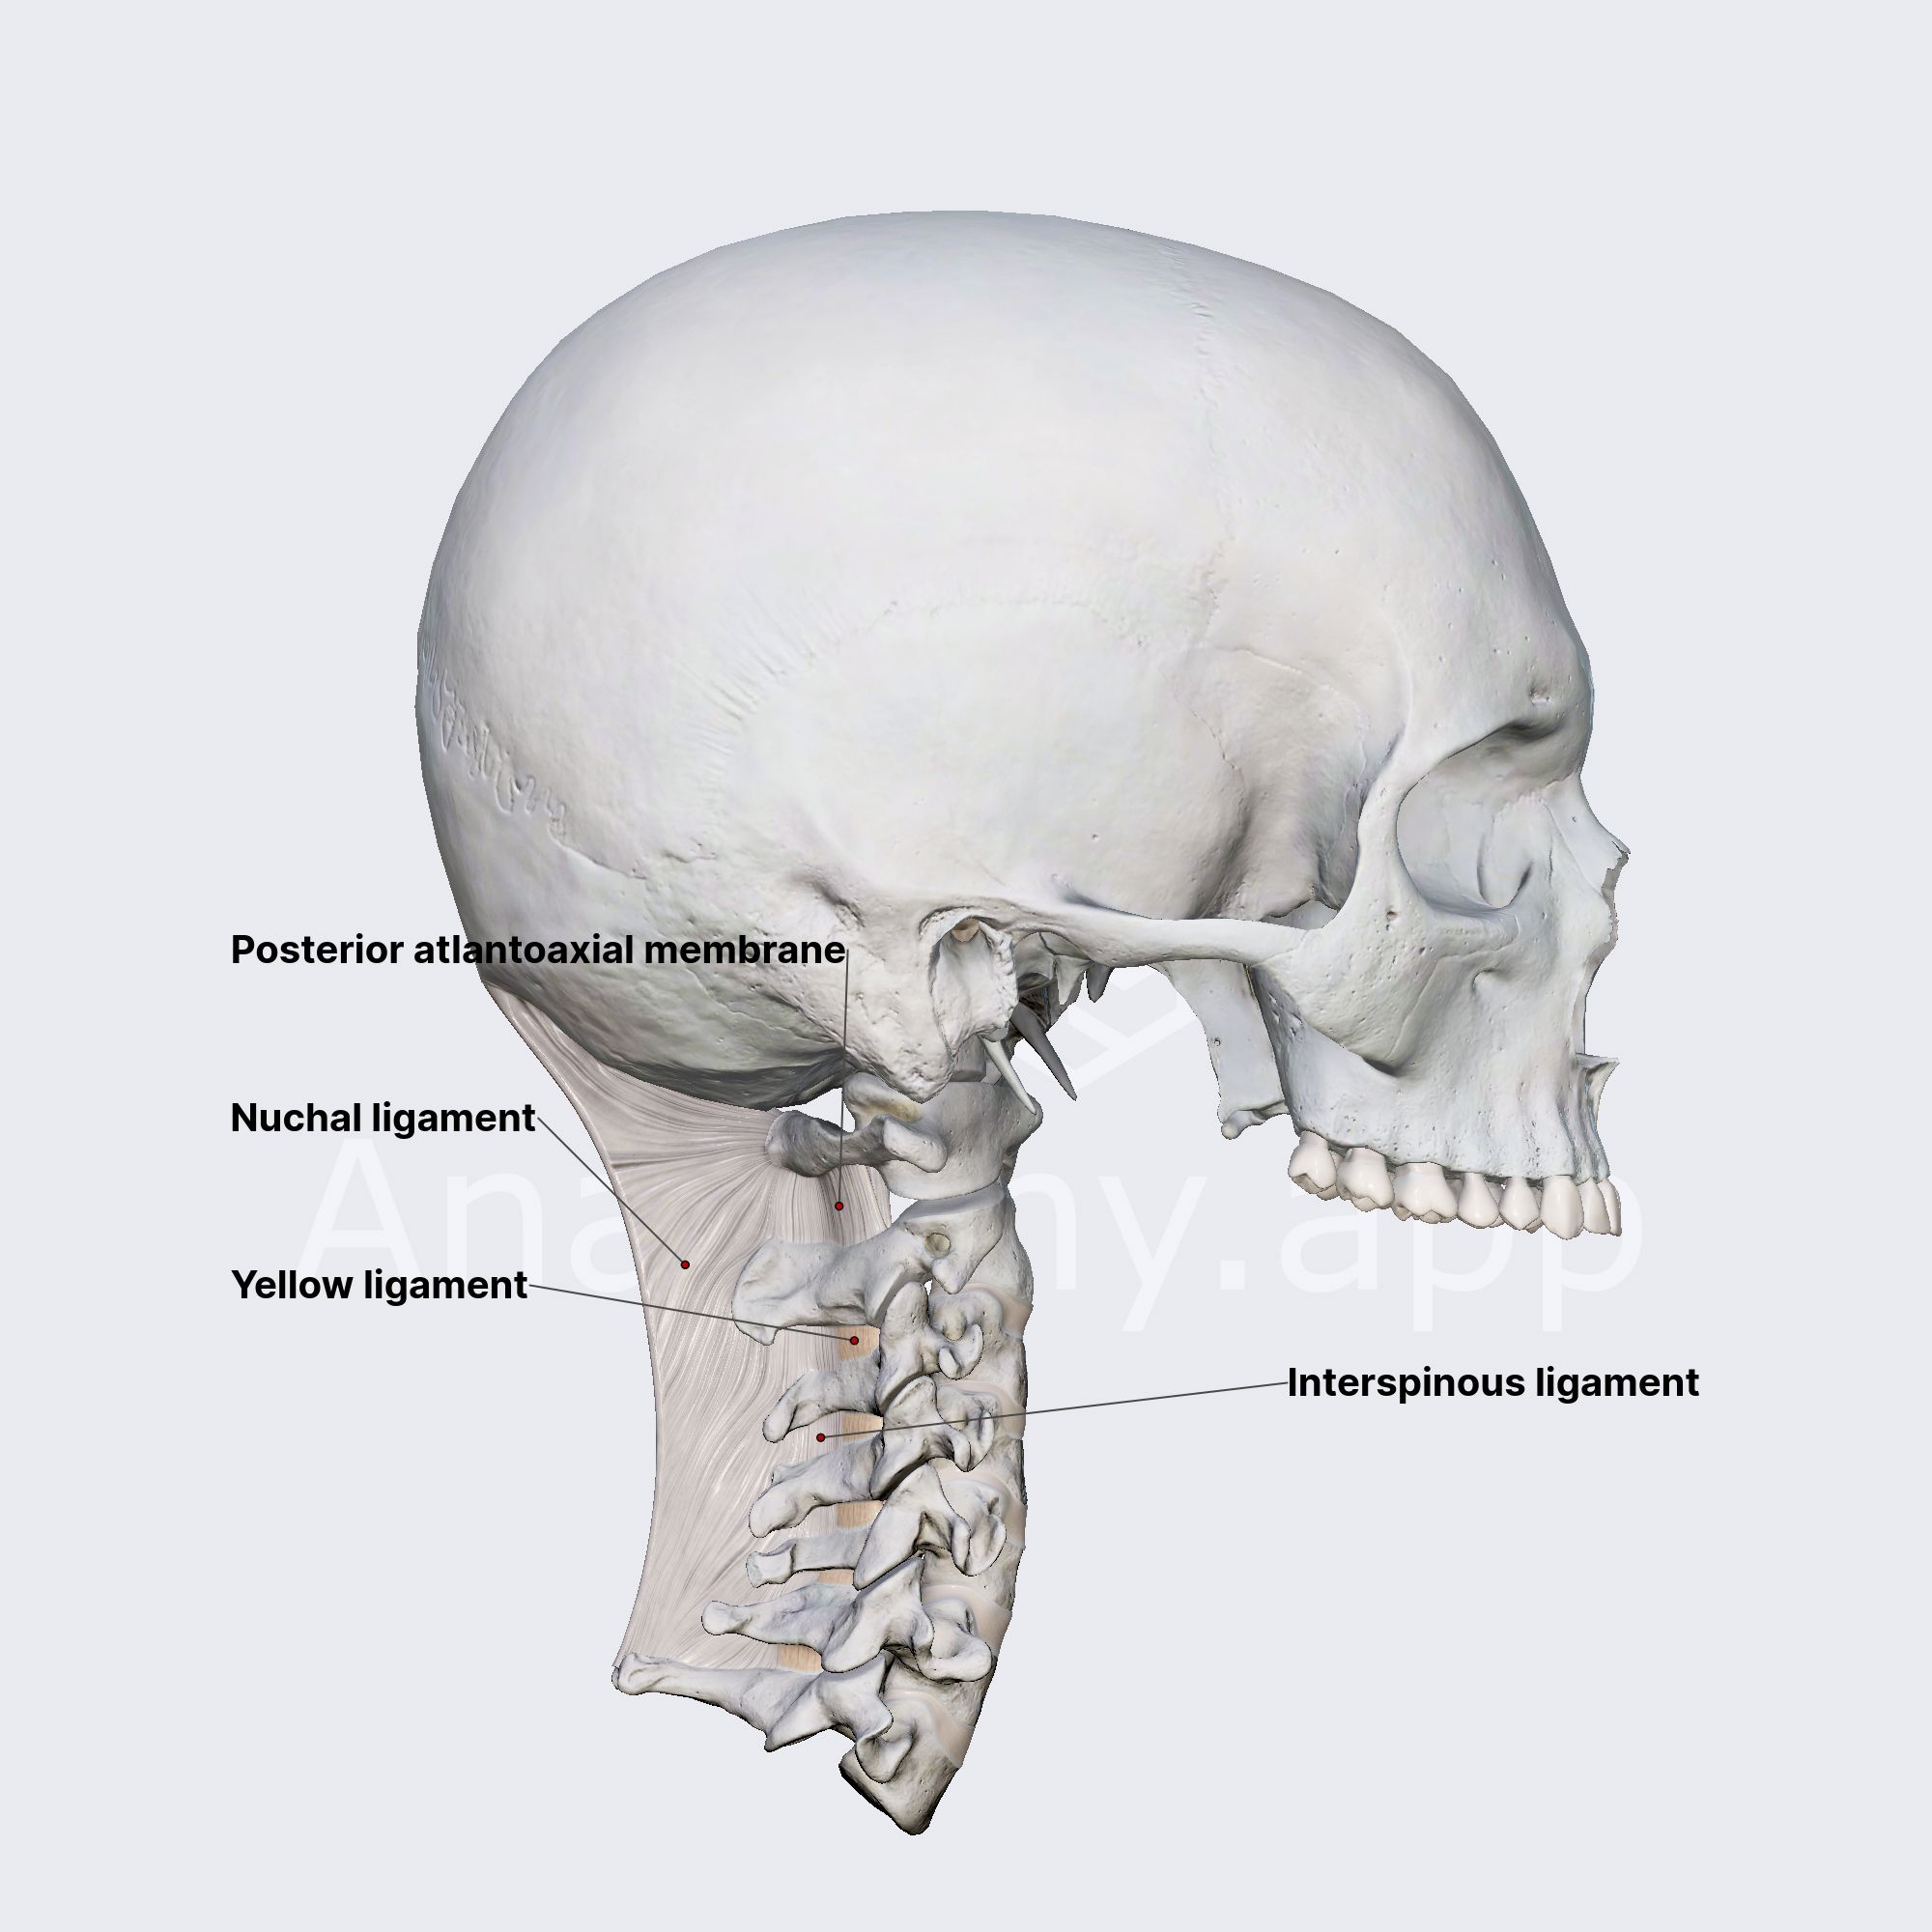

Do You Have Neck Pain? It Could Be Coming From Your Ligaments - Old Post Physical Therapy

Afraid to stick your neck out when it comes to naming cervical spine ligaments? Know the anterior longitudinal ligament (ALL) \u0026 that's ALL? Is the nuchal ligament a NEW CALL for you?